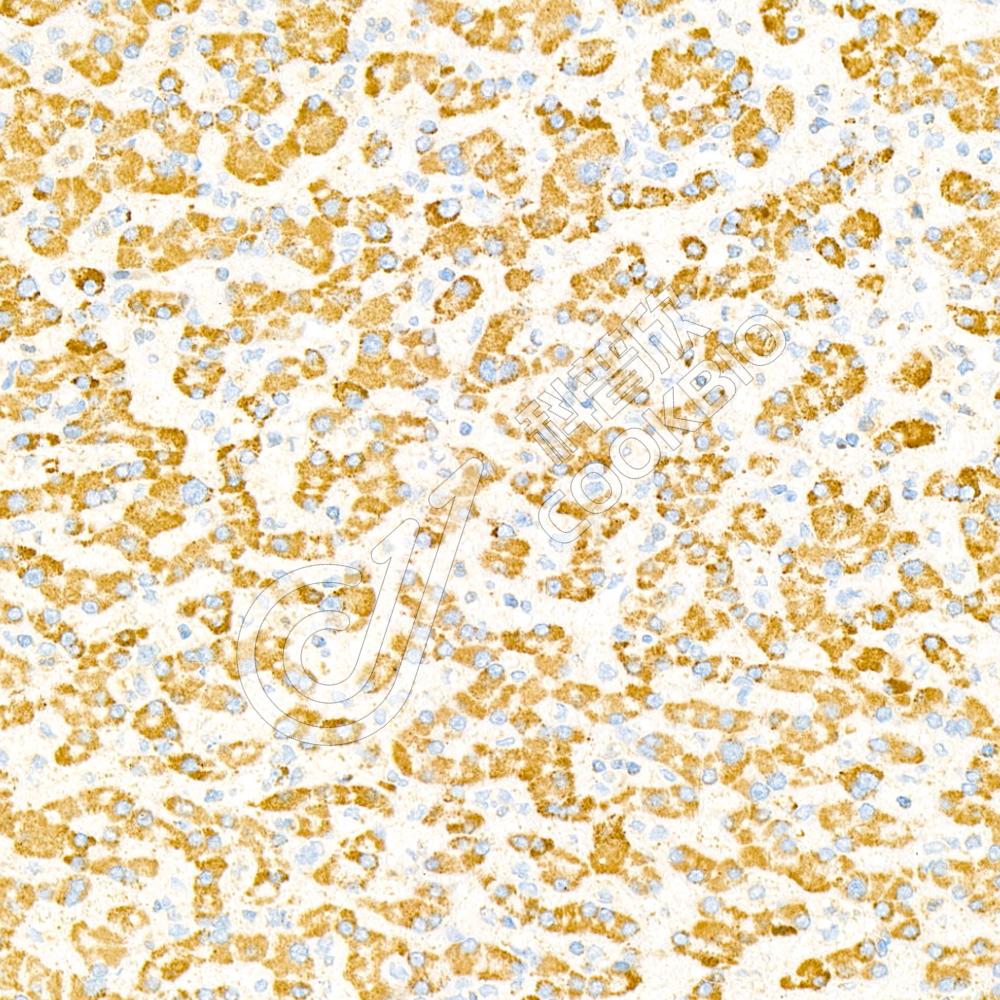

Glyceraldehyde 3-phosphate dehydrogenase (abbreviated as GAPDH or less commonly as G3PDH) is an enzyme of ~37kDa that catalyzes the sixth step of glycolysis and thus serves to break downglucose for energy and carbon molecules. In addition to this long established metabolic function, GAPDH has recently been implicated in several non-metabolic processes, including transcription activation, initiation of apoptosis, ER to Golgi vesicle shuttling, and fast axonal, or axoplasmic transport. In sperm, a testis-specific isoenzyme GAPDHS is expressed.